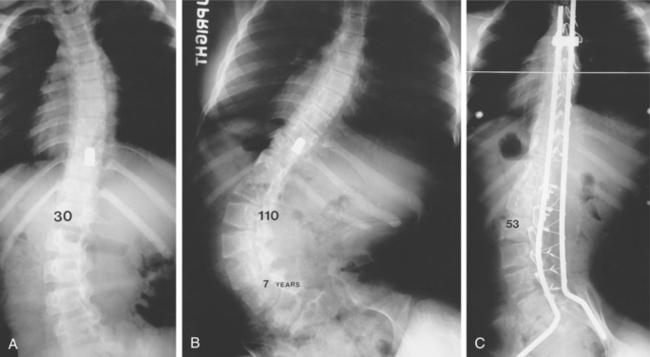

Skeletal Changes.: Joint ankylosis caused by heterotopic ossification, or ectopic bone formation in the soft tissue such as the tendons and connective tissue, can limit range of motion, cause pain, and impair seating and posture. It often develops near the large joints, such as the anterior area of the hip, knee, shoulder, and elbow. It is always found below the level of the lesion, and it begins to develop within the first year after injury. The initial symptoms are soft tissue swelling, pain, redness, and increased temperature in the affected area. Changes in bony alignment can develop secondary to muscle imbalances caused by unopposed contractions. Scoliosis can develop over time due to lack of paraspinal support, as is evidenced in Fig. 34-12.

Figure 34-12 Progressive paralytic scoliosis after gunshot wound. A, Initial curve of 30 degrees. B, Seven years later, curve is 110 degrees. C, After fusion and segmental instrumentation, correction to 53 degrees. (From Canale ST, ed: Campbell’s operative orthopaedics, ed 10, St Louis, 2003, Mosby.)